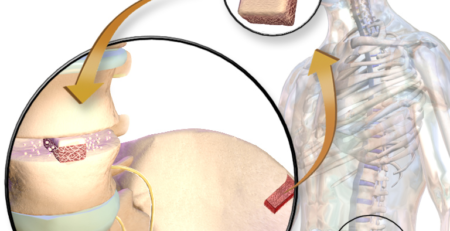

عملية الرباط الصليبي: كيف تُجرى؟

تعتمد عملية الرباط الصليبي الحديثة على عملية الرباط الصليبي المنظار، حيث يتم:

- إزالة بقايا الرباط التالف

- إنشاء قنوات عظمية دقيقة

- زرع طُعم (رقعة) جديد يحاكي وظيفة الرباط الطبيعي، ويمكنكم الاطلاع على مصادر الرقعة المستخدمة في اعادة بناء الرباط الصليبي بالنقر هنا.

- تثبيت الطُعم لضمان الثبات